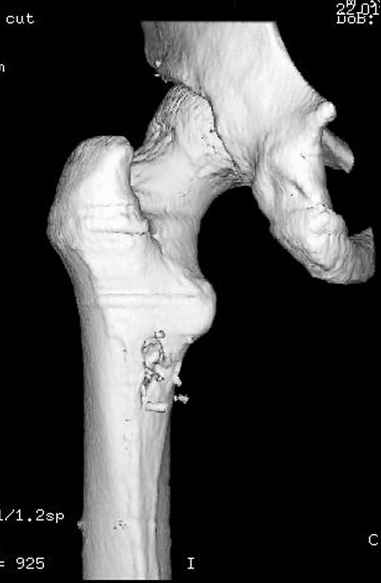

Больной с огнестрельным переломом бедра с вовлечением около 15% медиального кортекса, входное отверстие около 1 см в диаметре; стабильный, без сосудистых и неврологических признаков.

Литературные данные о влиянии кортикального дефекта на стрессовые переломы в длинных трубчатых костях в основном встречаются в онкологии, например кортикальный дефект более 50% имеет больше шанса стрессовых переломов, чем в нашем случае.

Учитывая, что больной получил травму не во время визита в церковь, и он является одним из представителем 40 миллионного “outstanding itizen”, без медицинской страховки, без работы в свои 39 лет, и без надлежающей ортопедической дисциплины у которого отсутсвует страх стрессового перелома, было рекомендовано оперативное лечение: профилактическое антеградное интрамедуллярное штифтование.

Методика штифтования при отсутствии большой зоны перелома как при онкологических профилактических штифтованиях, расверливание интрамедуллярного канала проводим с предварительным наложением дополнительного дренажного отверстия в дистальном отделе бедра (в данном случаи в канале оставили 6.5 мм канюлированный шуруп), иначе при создании давления в канале во время сверления имеется опасность эмболизации легочной артерии тромбом.